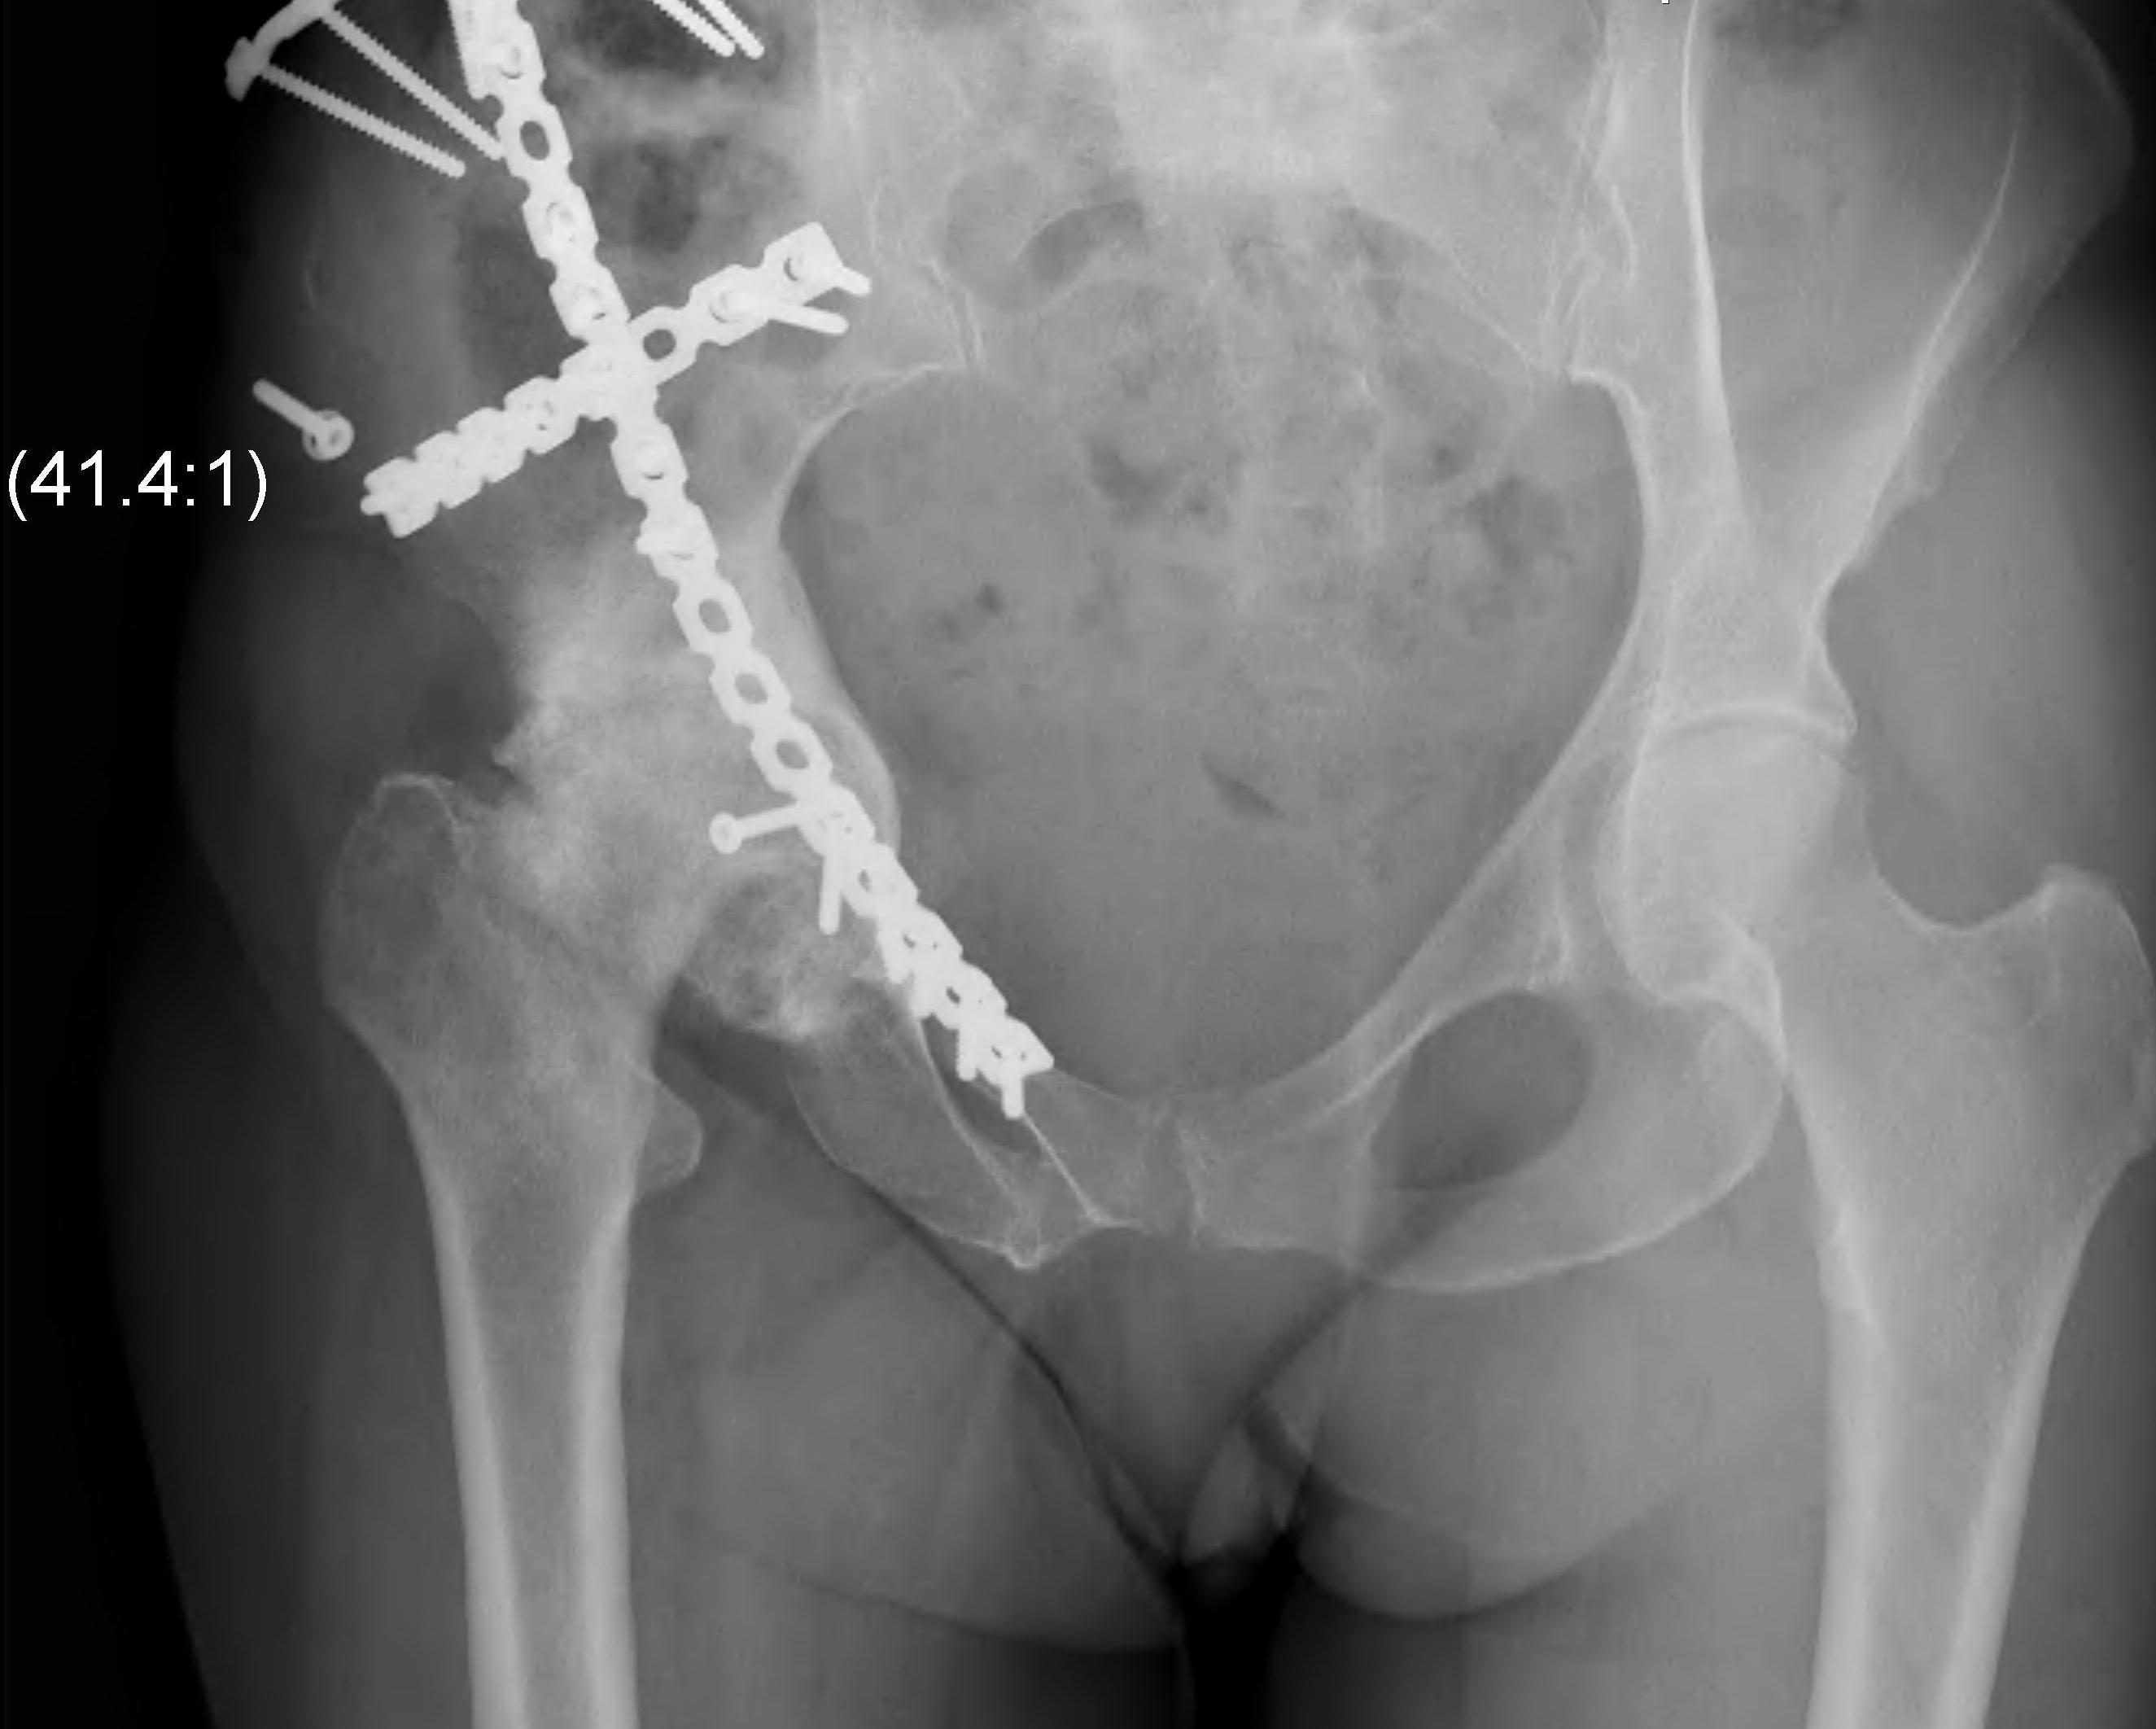

ORIF

1. Reduce quadrilateral plate

- small T plate / will sit under pelvic reconstruction plate

- separate recon plate

2. Plate iliac crest fracture

- long 13 hole plate from pubis

- along superior pubic ramus up onto inner table of ilium

- indirect acetabular reduction

Options

1. Posterior / Kocher-Langenbeck approach

- posterior column / wall

2. Ilioinguinal approach

- anterior column / wall